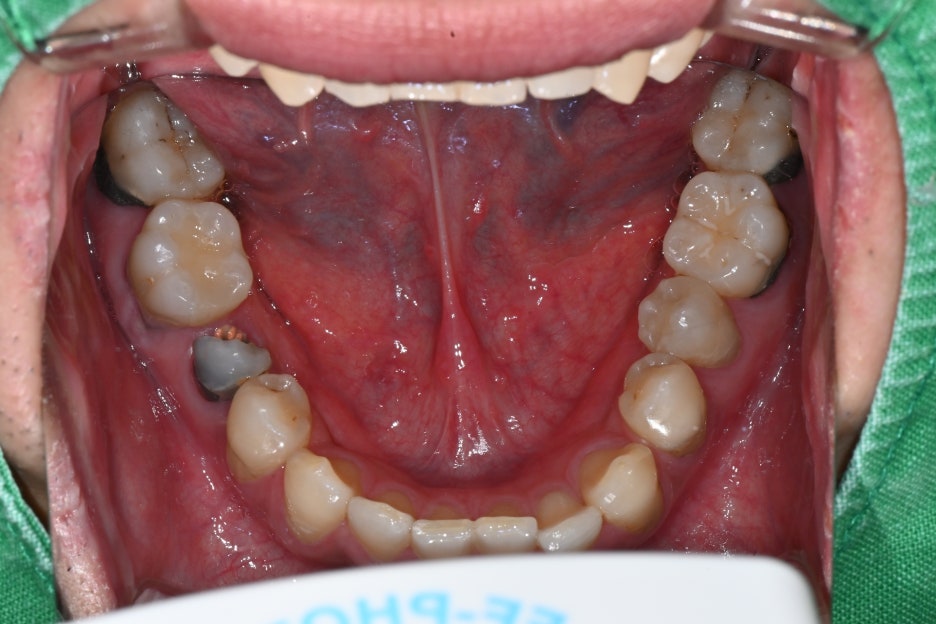

Photo at the first visit

Since the lower right molar broke, chewing causes pain

and discomfort.

Panoramic imaging showed that the lower right molar had fractured

and could not be preserved.